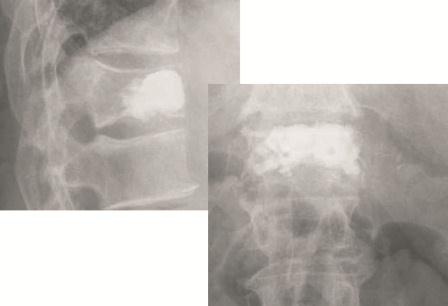

Kyphoplastie: Einfache osteolytische Metastasen können auch bei Hinterkantenbeteiligung üblicherweise bei entsprechenden Vorsichtsmaßnahmen mit der von uns bevorzugten Shieldkyphoplastie versorgt werden (Abb. 1a und b). Die reine Vertebroplastie erscheint uns in diesen Fällen zu riskant. Mit der Shieldkyphoplastie können wir die Osteolyse monopedikulär mit dem gebogenen Bohrer sehr gut adressieren und das Shield-Implantat genau dort platzieren. Perforationen im Shieldimplantat, aus denen der Zement gerichtet nach ventral austreten kann, stellen die Interdigitation mit der umliegenden Spongiosa sicher, wodurch die Stabilität erhöht wird.